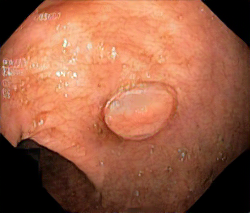

We have used a polyp dataset published with HyperKvasir dataset [51], which consists of polyp findings extracted from endoscopy examinations. HyperKvasir contains polyp images with corresponding segmentation masks annotated by medical experts. We use only this polyp dataset as a case study because of the time and resource-consuming training process of the SinGAN-Seg pipeline. However, the SinGAN-Seg model and pipeline can be used for any segmentation dataset.

A few sample images and the corresponding masks of the polyp dataset in HyperKvasir are shown in Fig 2. The polyp images are RGB images. The masks of the polyp images are single-channel images with white () for true pixels, which represent polyp regions, and black () for false pixels, which represent clean colon or background regions. In this dataset, there are different sizes of polyps. The distribution of polyp sizes as a percentage of the full image size is presented in the histogram plot in Fig 3, and we can observe that there are more relatively small polyps compared to larger polyps. Additionally, a subset of this dataset was used to prove that the performance of segmentation models trained with small datasets can be improved using our SinGAN-Seg pipeline, and the whole dataset was used to show the effect of using SinGAN-Seg generated synthetic images instead of a large dataset which has enough data to train segmentation models. In this regard, this dataset was used for two purposes: